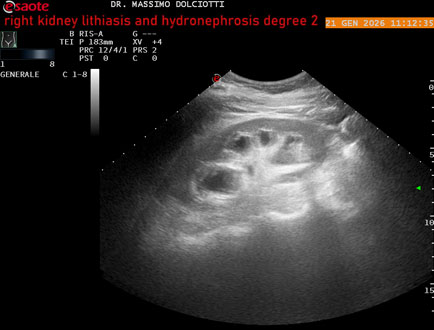

Data inserimento: 22/01/2026

Ecografia del: 21/01/2025

Strumento: Esaote MyLab Eight

Sonda: Convex Multifrequenza 1-8 MHz

Età Paziente: M 27 anni

Motivazione dell'esame: dolore al fianco destro da 3 mesi.

Commento all'esame: le immagini ed il video documentano il rene destro in sede, con ecostruttura disomogenea per evidenza, alla pelvi renale, di immagine iperecogena delle dimensioni di 16,2 mm, con cono d'ombra posteriore, da ricondurre a litiasi ed una formazione simile, di minore entità, al polo inferiore, delle dimensioni di 6,8 mm. Rene dx con diametro longitudinale di 122 mm (v.n. 90-120 mm) x 63 mm e parenchima renale dello spessore di 15 mm (v.n. > 13 mm). Rene dx con idronefrosi di 2° grado.

Conclusioni: litiasi e idronefrosi di 2° grado al rene destro (lithiasis and second-degree hydronephrosis of the right kidney).

In collaborazione: Dr.ssa Marica Manfredi - Ancona, Dr. Ilir Qose - Ancona

Presentazione: Dr. Massimo Dolciotti - Ancona

Elaborazione digitale: Andrea Dini - Ancona